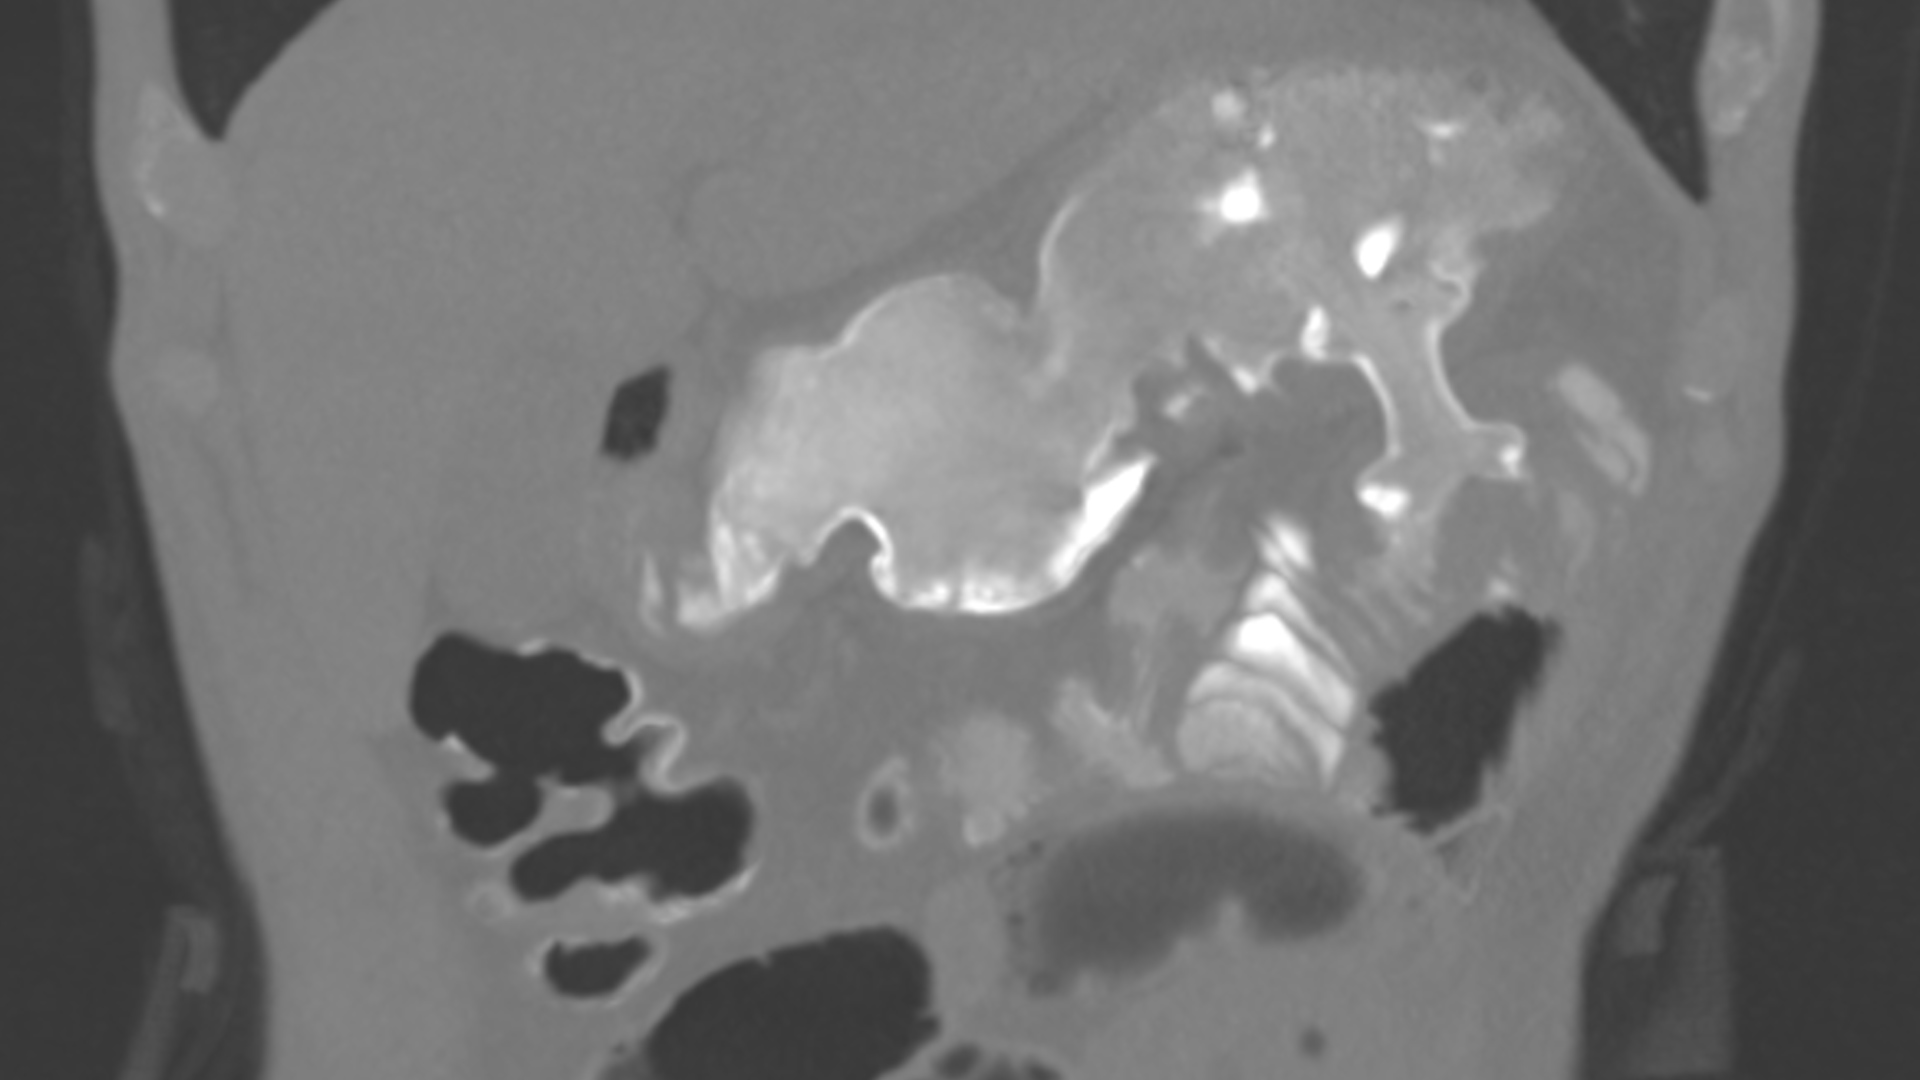

Tomografia computerizată (CT) cu substanță de contrast a evidențiat o îngroșare duodenală de până la 17 mm pe o lungime de până la 5 cm în adiacența regiunii cefalice pancreatice, cu ușoară dilatație și stază în amonte de leziune, cu densificare a grăsimii peritoneale și fine fuzee lichidiene. Regiunea cefalică pancreatică cu dimensiuni ușor crescute, însă cu priză de contrast omogenă.

Ecoendoscopic a fost vizualizat un pancreas cu criterii de pancreatită cronică (Rosemont 1 major și 3 minore), cu perete duodenal îngroșat, cu ecostructură neomogenă, cu prezența unei formațiuni chistice de 5 mm în grosimea peretelui (Fig. 1). S-a decis plasarea unei sonde nazoenterale pentru alimentația pacientului, alimentație enterală care a fost bine tolerată, cu un câștig ponderal pe parcursul a 3 săptămâni de circa 3kg.